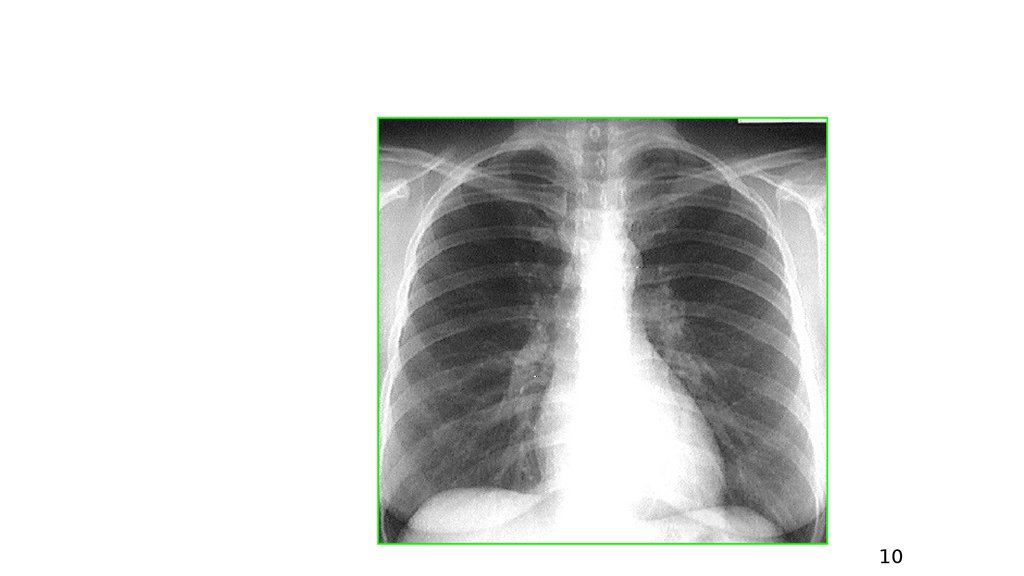

Рентгенограмма органов грудной клетки в прямой проекции

2. Рентгенограмма органов грудной клетки в прямой проекции

10